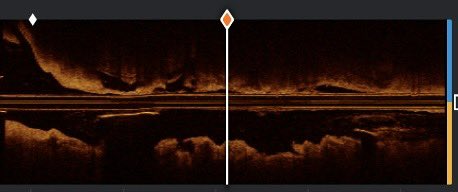

Challenging case: Heavy calcified mid RCA with eruptive nodule. Pre-PCI OCT insights were crucial to navigate this safely. Using Rota-shock with an excellent result. @ziadalinyc @DrNataliaP @mirvatalasnag @MauroEchavPinto @hect2701 @cecyefox @misamed @JEscaned #CardioTwitter